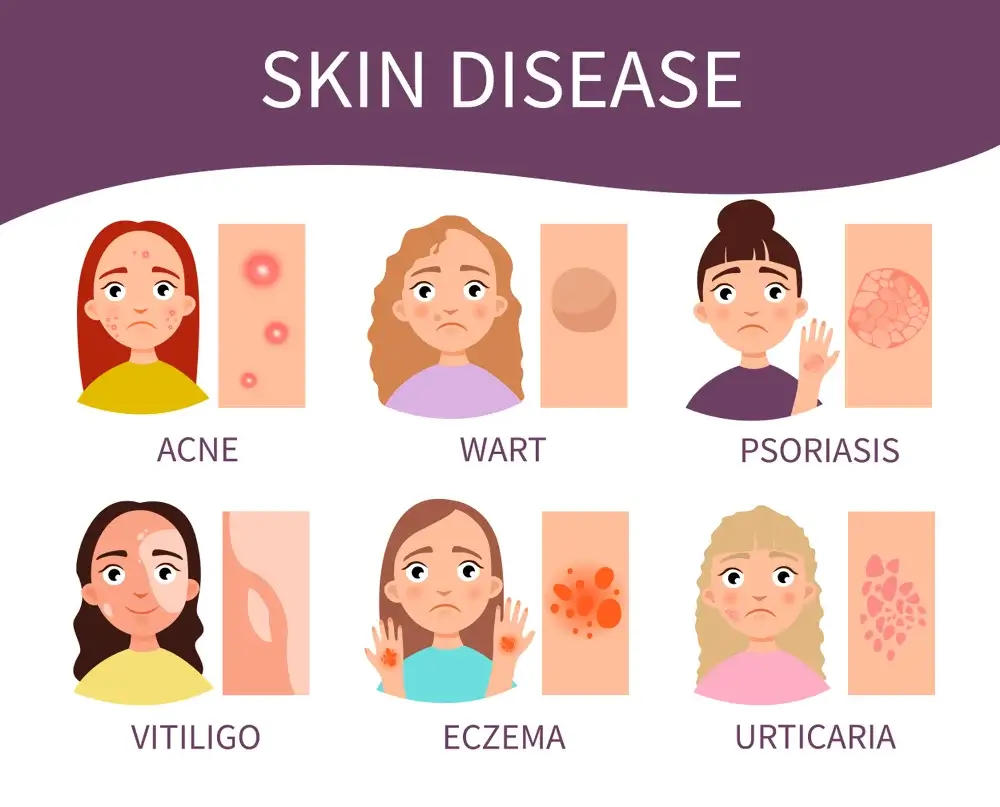

Skin Disease such as Acne and Eczema:

Acne and eczema are common skin conditions that can be difficult to treat. Acne is a skin condition that affects the face, neck, chest, and back. Eczema is a skin condition that affects the skin anywhere on the body. It can be itchy, dry, and red. Both conditions can cause discomfort and social embarrassment. Treatment for acne and eczema generally involves using topical medications, but often these treatments are not effective over the long term.